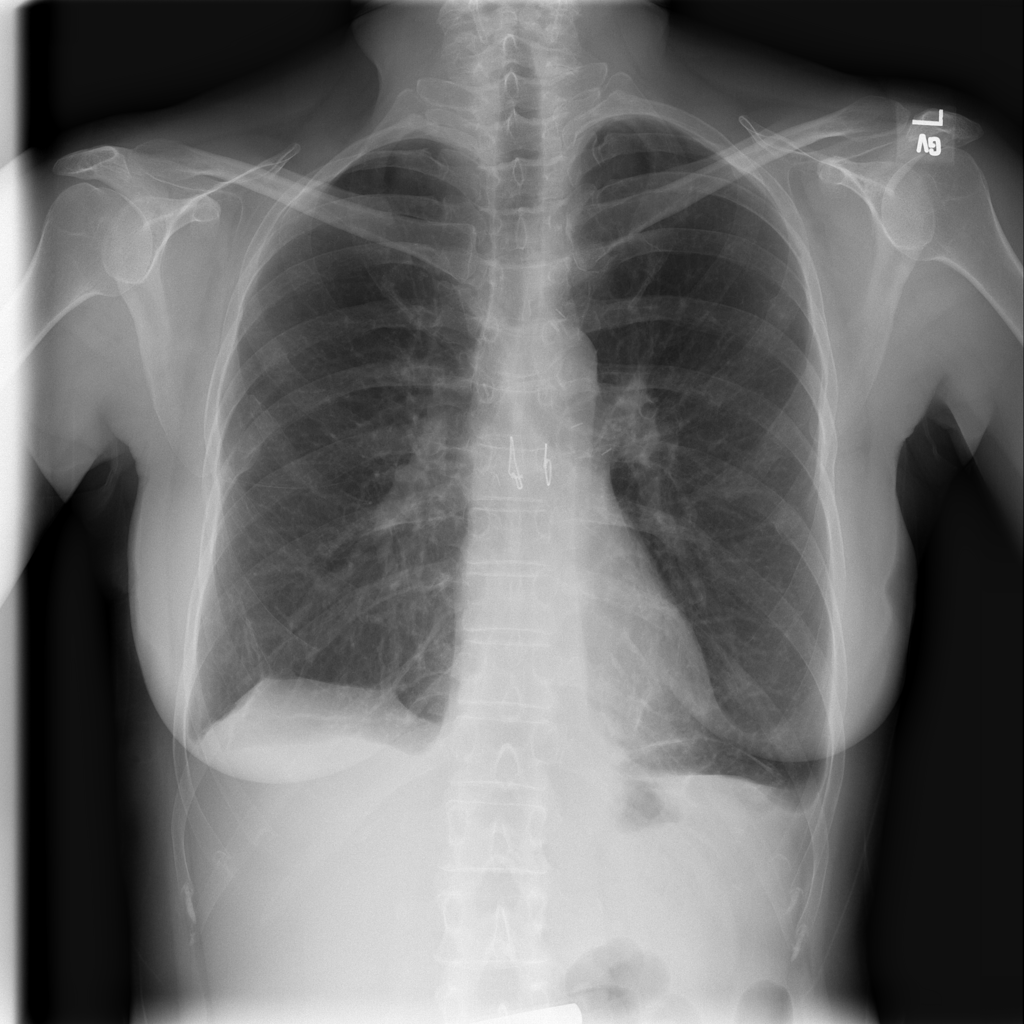

PAT-4639 · IMG-013Pneumothorax

PAT-4639 · IMG-013

AP